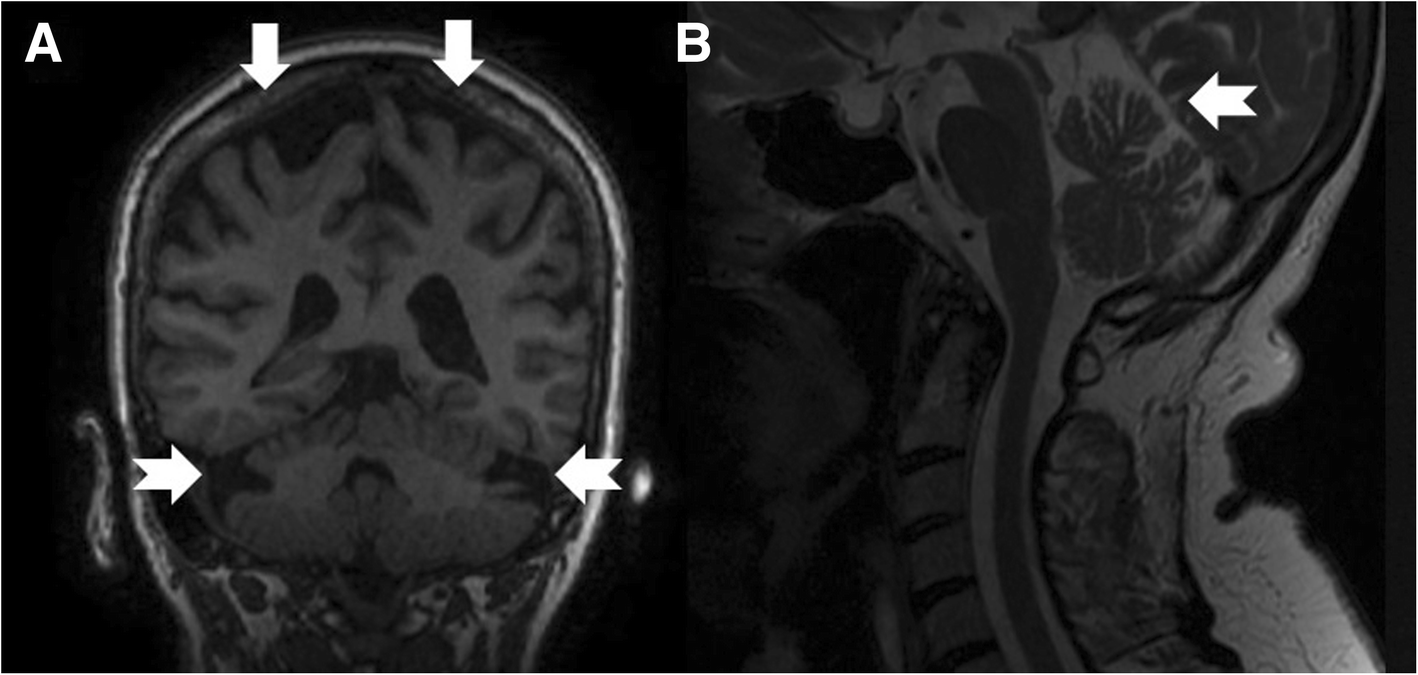

Coronal T1-weighted (a), mid-sagittal T2-weighted (b) of patient 5 at age 76. Note atrophy in the bi-parietal brain regions (thick arrows) as well as lateral hemispheres and superior vermis of the cerebellum (notched arrows)